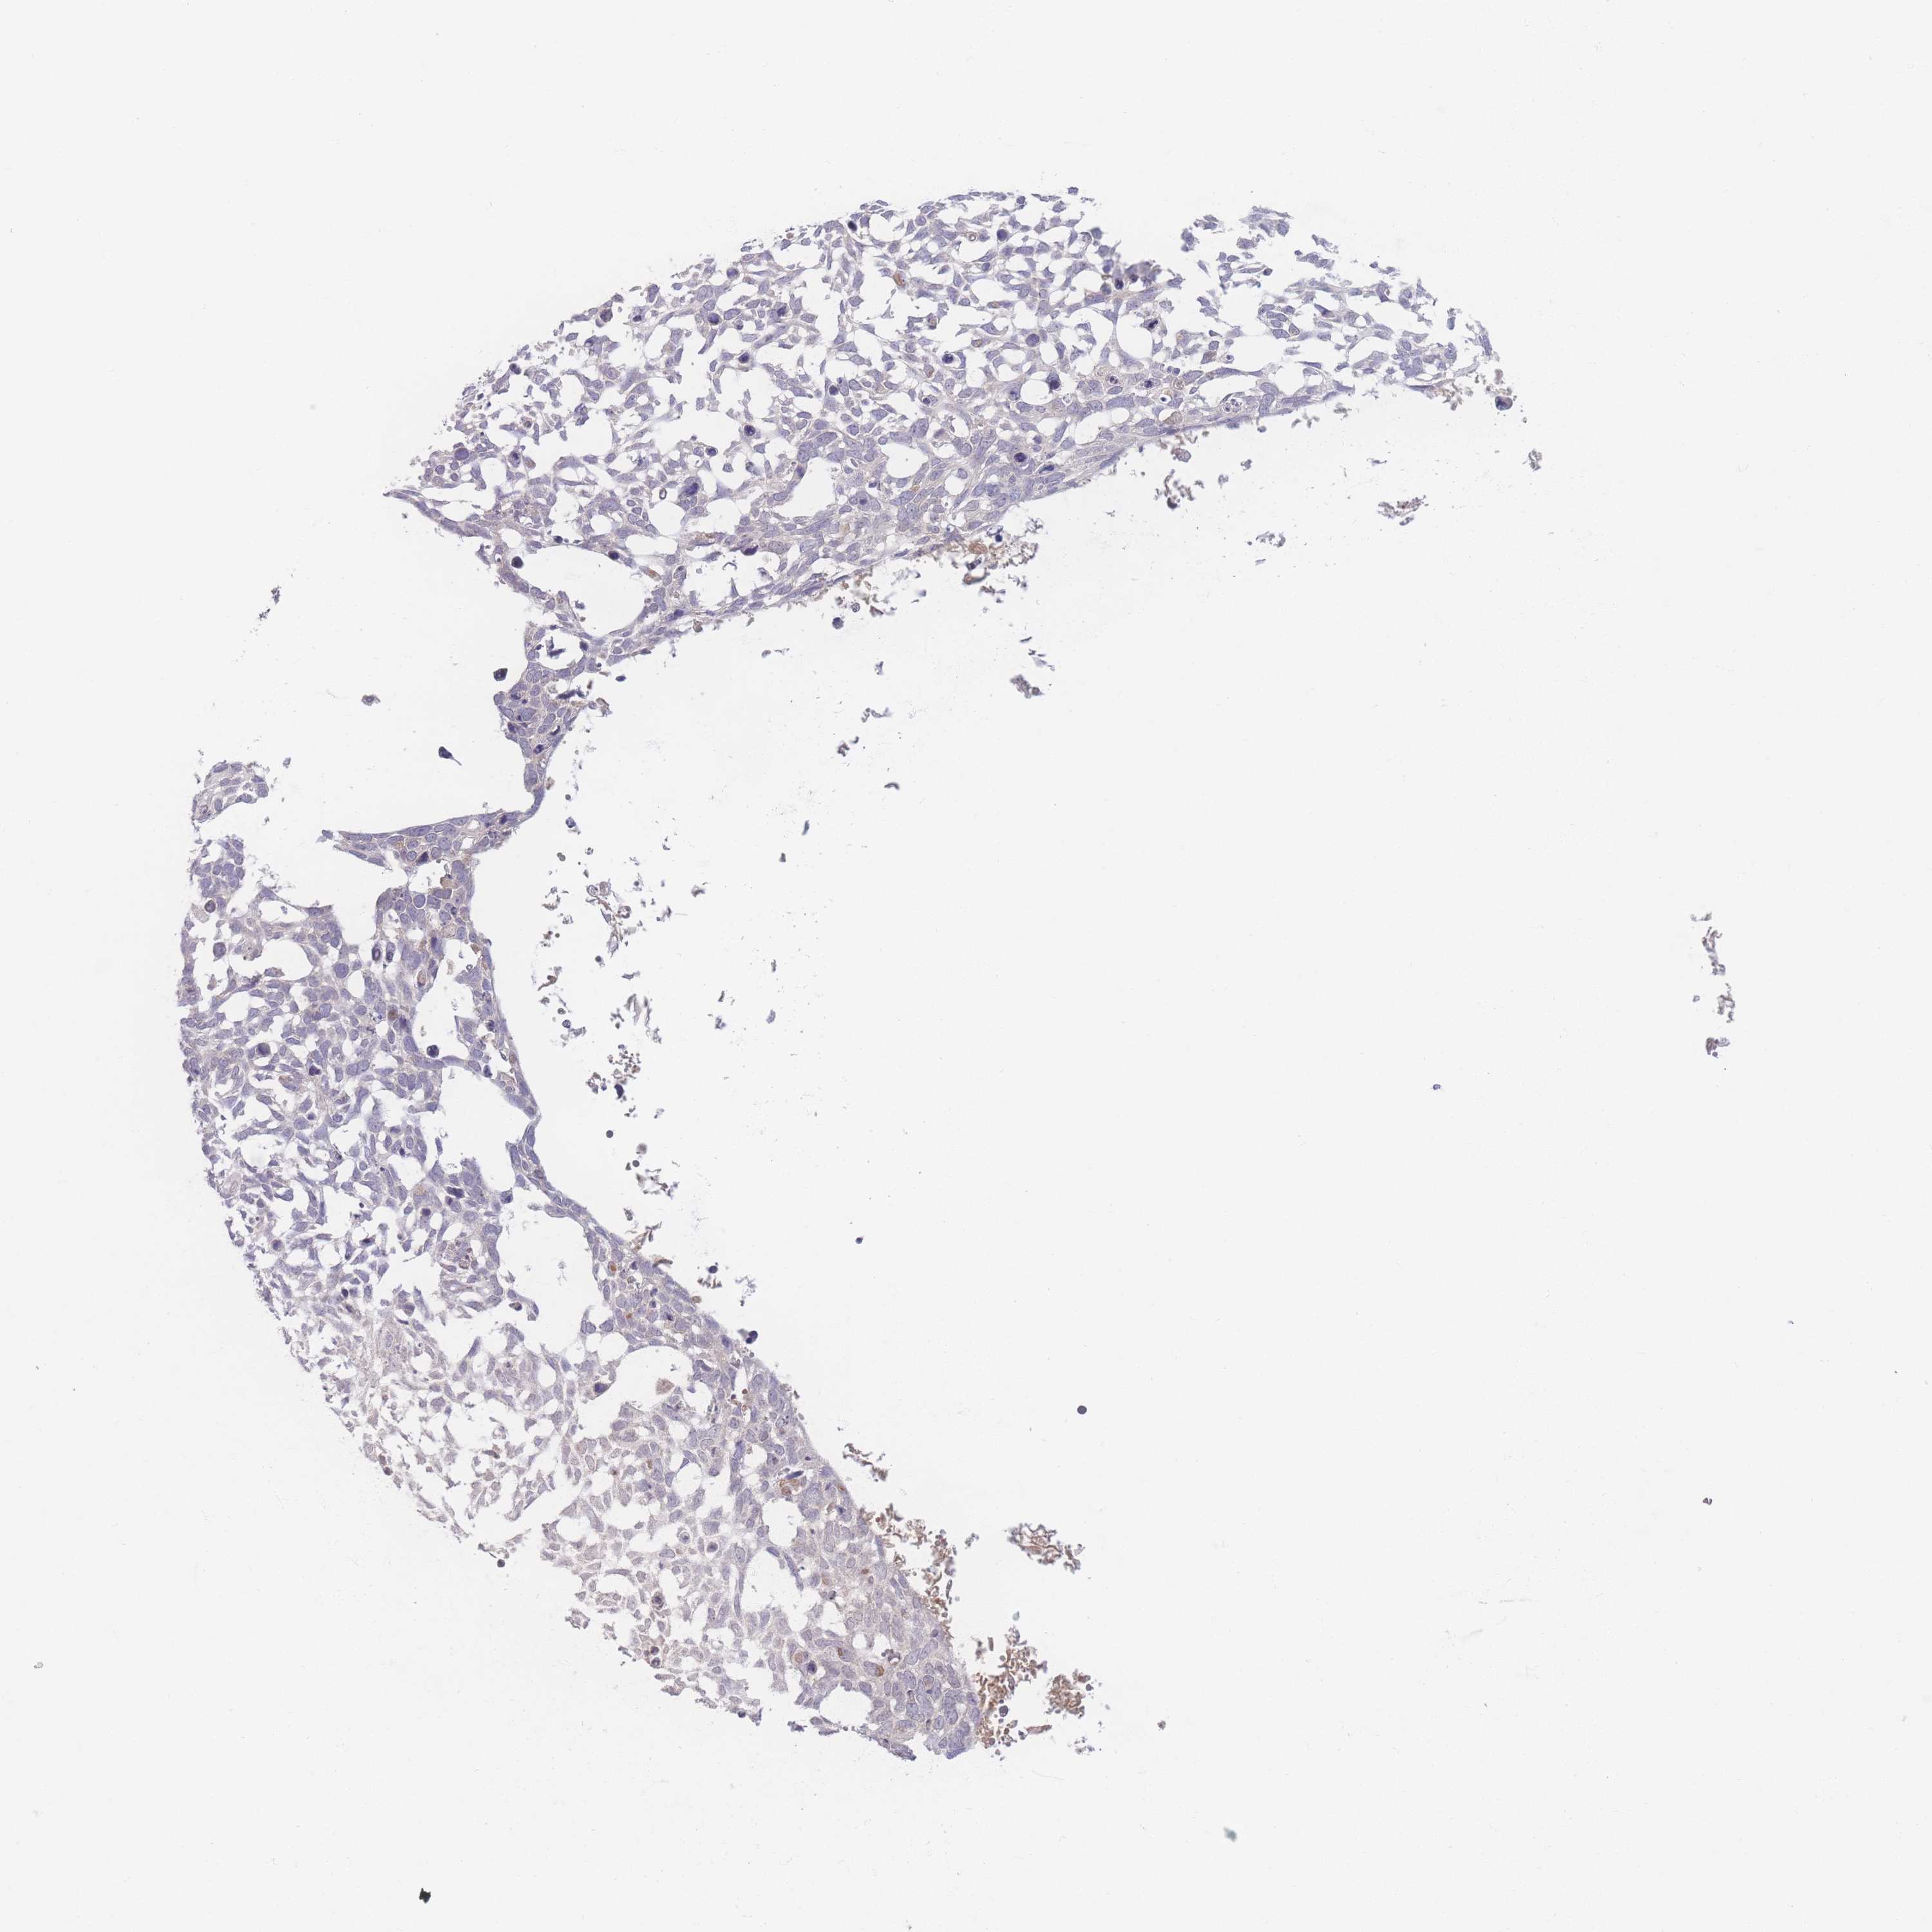

Basal cell and squamous cell cancer

SKIN CANCER - Protein expressioni

A mouse-over function shows sample information and annotation data. Click on an image to view it in a full screen mode. Samples can be filtered based on level of antibody staining by selecting one or several of the following categories: high, medium, low and not detected. The assay and annotation is described here.

Antibody stainingi

Antibody staining in the annotated cell types in the current human tissue is reported as not detected, low, medium, or high, based on conventional immunohistochemistry profiling in selected tissues. This score is based on the combination of the staining intensity and fraction of stained cells.

Each image is clickable and will lead to virtual microscopy that enables deeper exploration of all samples and also displays staining intensity scores, fraction scores and subcellular localization as well as patient and tissue information for each sample.

Antibody HPA036302

Staining

High

Medium

Low

Not detected

Intensity

Strong

Moderate

Weak

Negative

Quantity

>75%

75%-25%

<25%

None

Location

Nuclear

Cytoplasmic/membranous

Cytoplasmic/membranous,nuclear

Basal cell carcinoma